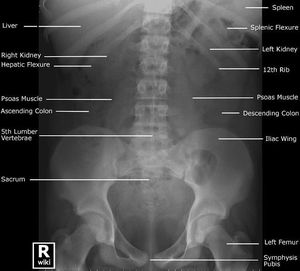

Labeled Plain X-Ray of the abdomen